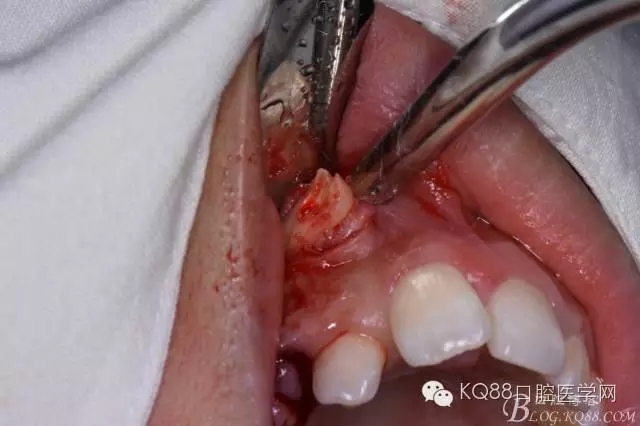

圖5. 翻瓣

圖6.去骨

圖7.暴露出13牙冠

圖8.高速渦輪機分牙、目的是盡量少去骨。

圖9. 從頸部截分13

圖10. 13牙冠頸部分牙情況

圖11.再把牙冠分成近中、遠中兩部分。